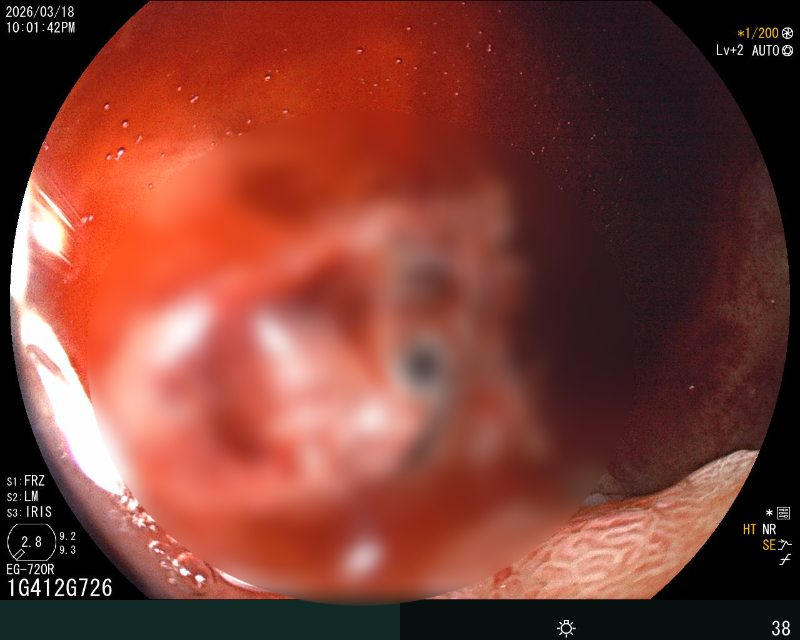

十二指肠球部冰盐水+去甲肾冲洗

在重症医学科(ICU)团队严密监护保障下,消化科内镜团队克服患者休克、体位受限等困难,紧急开展床旁急诊胃镜。镜下可见出血病灶位于十二指肠球部出现糜烂渗血,一处8×4mm 深溃疡覆血痂及污苔,活动性渗血明显,且黏膜严重水肿、肠腔狭窄,内镜镜身不能通过,操作难度极大。内镜团队通过精准操作,利用去甲肾上腺素联合冰盐水反复冲洗创面,收缩血管减少出血,再通过内镜通道将止血粉均匀喷洒于糜烂及溃疡面。药物覆盖后,渗血即刻停止,创面形成稳定保护层,成功止血。次日胃镜复查显示,患者溃疡创面已覆盖厚白苔,活动性渗血完全消失,黏膜水肿显著消退,肠腔狭窄改善,止血效果确切,为后续抗感染、纠正休克等综合治疗赢得关键时间。目前患者生命体征平稳,未再出现消化道出血。